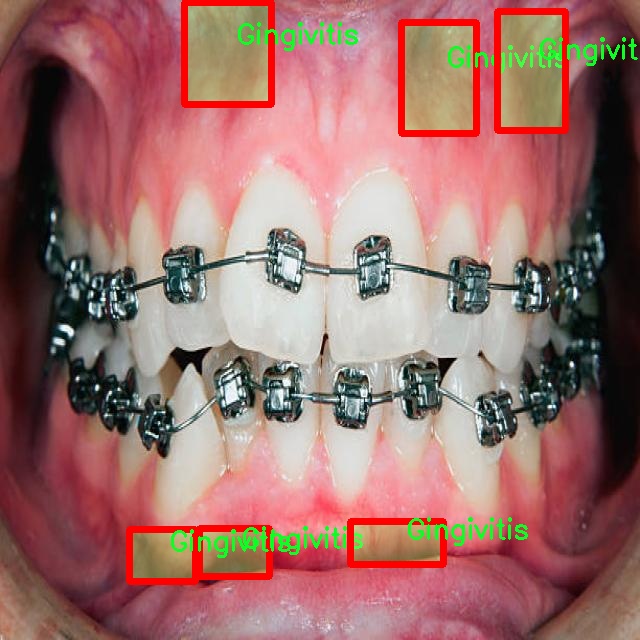

图片效果

在这里插入图片描述

在本研究中,我们使用了名为“unbeknownst to man”的数据集,旨在改进YOLOv8-seg的口腔疾病图像分割系统。该数据集专注于口腔健康领域,涵盖了四种主要的口腔疾病类别,分别是龋齿(Caries)、牙龈炎(Gingivitis)、牙齿变色(Tooth Discoloration)和溃疡(Ulcer)。这些类别的选择不仅反映了口腔疾病的多样性,也为我们提供了一个全面的视角,以便更好地理解和分析这些疾病的表现形式及其在图像中的特征。

数据集中的每个类别都包含大量高质量的图像,这些图像经过精心标注,确保了每个样本的准确性和一致性。龋齿作为最常见的口腔疾病之一,其图像展示了不同阶段的龋齿发展,从初期的微小白斑到严重的牙体损坏,图像中清晰的细节为模型训练提供了丰富的信息。牙龈炎则通过展示红肿、出血等症状,帮助模型学习如何识别和分割出受影响的牙龈区域。牙齿变色的图像则展示了因多种因素导致的牙齿色泽变化,这些变化可能是由于饮食、生活习惯或口腔卫生不良等原因引起的。最后,溃疡的图像则提供了对口腔内病变的直观表现,通常伴随着疼痛和不适,这类图像的标注对于识别和分割至关重要。